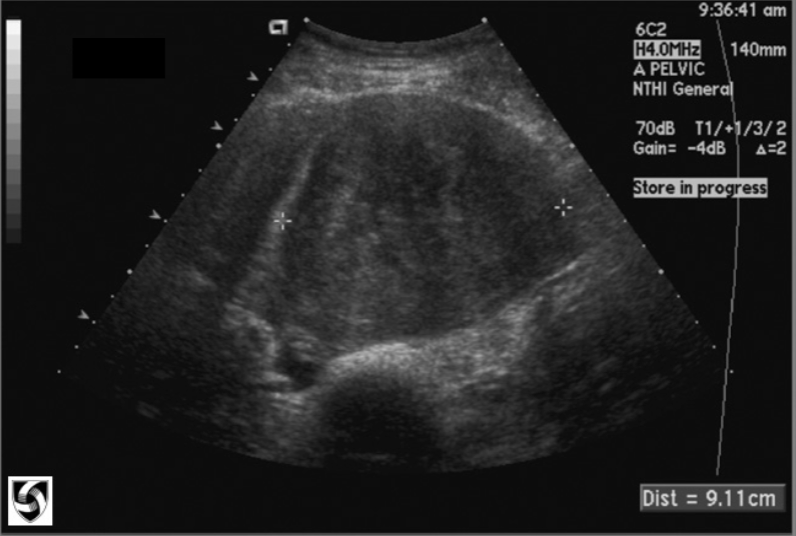

Ovarian Cysts

Most fluid-filled pelvic masses are ovarian in origin

Ovarian Cyst U/S appearance:

Assess: Size, Location, Composition, and Age of Patient

Smooth, well-defined borders

Absence of internal echoes

Increased posterior enhancement